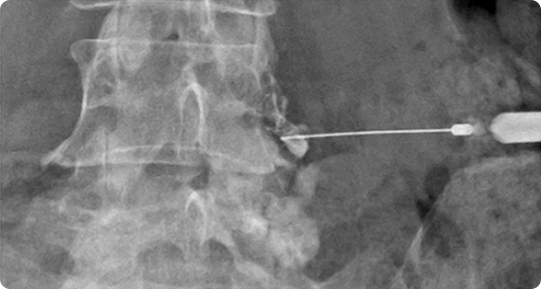

고주파수핵감압술

고밀도 이온확장(플라즈마장)을 쏘아 척추신경을 압박하는 디스크 내 분자를 수축ㆍ응고시키는 치료법입니다.

디스크(추간판)에 특수 바늘을 삽입하여 고주파 열에너지를 가하여 돌출된 디스크를 감압시키거나 통증을 유발시키는 동척추신경을 선택적으로 치료하는 비수술적 척추 치료법입니다. 기구의 끝 부분만 열이 발생하기 때문에 주변 조직이 손상될 위험이 적고, 병변 부위의 디스크만 선택적으로 감압하여 치료할 수 있습니다.

고주파로 튀어나온 디스크를 수축ㆍ응고시키거나 신경을 압박해 통증을 일으키는 좁아진 척추관을 넓혀주고 유착이 생긴 부분을 박리ㆍ제거하는 한편 염증과 부기를 가라앉히는 치료법입니다.